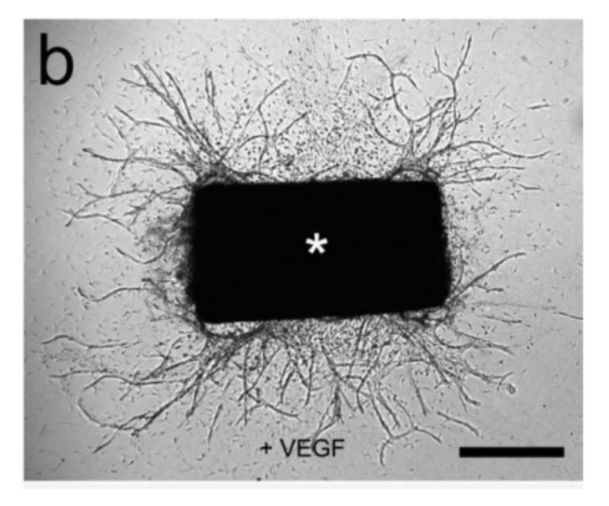

血管新生是由原有血管形成的新血管,在器官发育、再生和肿瘤发展过程中起着重要作用。基于球体的出芽实验可用于研究遗传改变或药理化合物对原代培养内皮细胞毛细血管样小管形成的影响。该方法的主要优点是可以在三维环境中研究血管生成。内皮细胞作为悬滴培养形成球体,这些球体嵌入胶原基质,24 小时后分析管的形成。通过分析芽数和芽长,可以研究基因操作或药物处理对血管生成的影响。

与现有的血管生成模型相比,主动脉环实验有许多优点。与分离的内皮细胞不同,主动脉外植体的固有内皮细胞没有经过多次培养而改变,并保留了其原有的特性。血管生成反应可以被血管生成调节剂抑制或刺激,并通过分子或免疫化学方法进行分析,而不受血清的干扰。血管生成出芽发生在周细胞、巨噬细胞和成纤维细胞存在的情况下,不同发育阶段的新生血管的超微结构可以通过电子显微镜进行评价。血管生成反应可以随时间定量,生成微血管生长曲线。用病毒构建物转染或从转基因小鼠获得的主动脉环可用于研究特定基因产物对血管生成反应的调节作用。